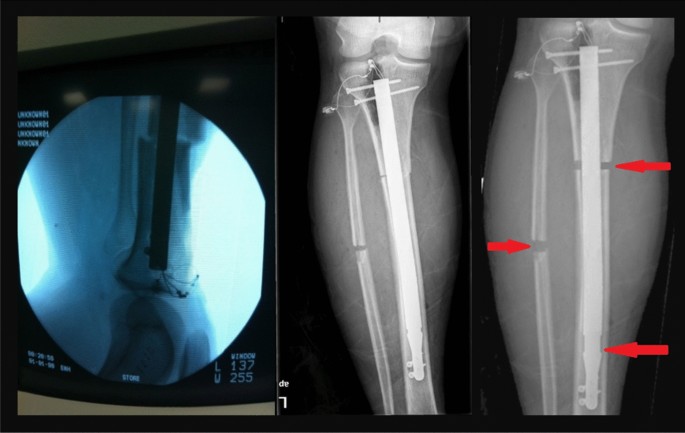

Mutare – Patients requiring surgery for broken limbs at government hospitals are struggling to receive timely treatment due to a shortage of intramedullary nails, a crucial surgical implant for bone fractures. Dr. Hillary Makiwa, an official at Victoria Chitepo Provincial Hospital, confirmed the crisis, stating that the government does not supply the implants due to high costs.

“There are no intramedullary nails in any government hospital. Patients are required to buy them from private pharmacies, where they cost around $350. The government cannot afford to supply them in every hospital,” said Dr. Makiwa.